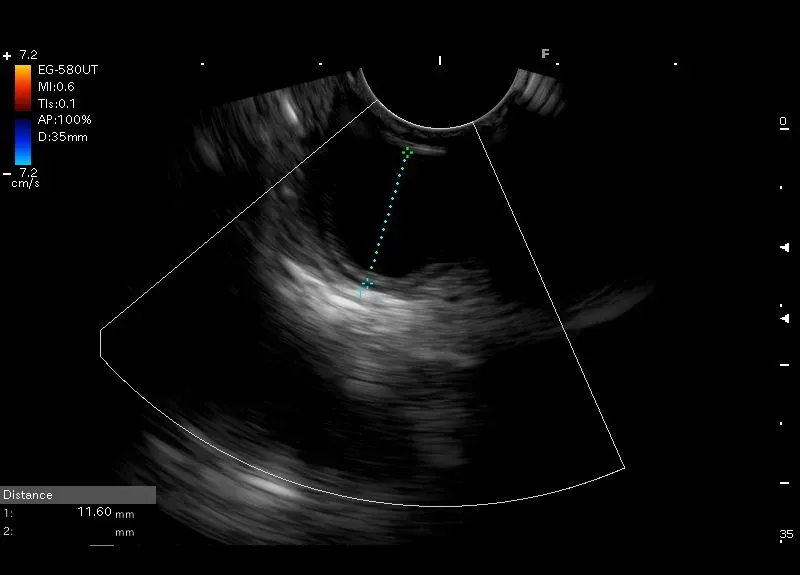

Badanie u dziecka, u którego w okolicy przedodźwiernikowej uwidoczniono zmianę opisaną jako podnabłonkowa, wielkości około 10 mm.

W obrazie  endosonograficznym zmianie tej odpowiada owalna przestrzeń bezechowa średnicy około 12 mm, dobrze odgraniczona wyraźną torebką z hyperechogenicznym wzmocnieniem za zmianą – obraz odpowiada obrazowi  torbieli ściany żołądka.